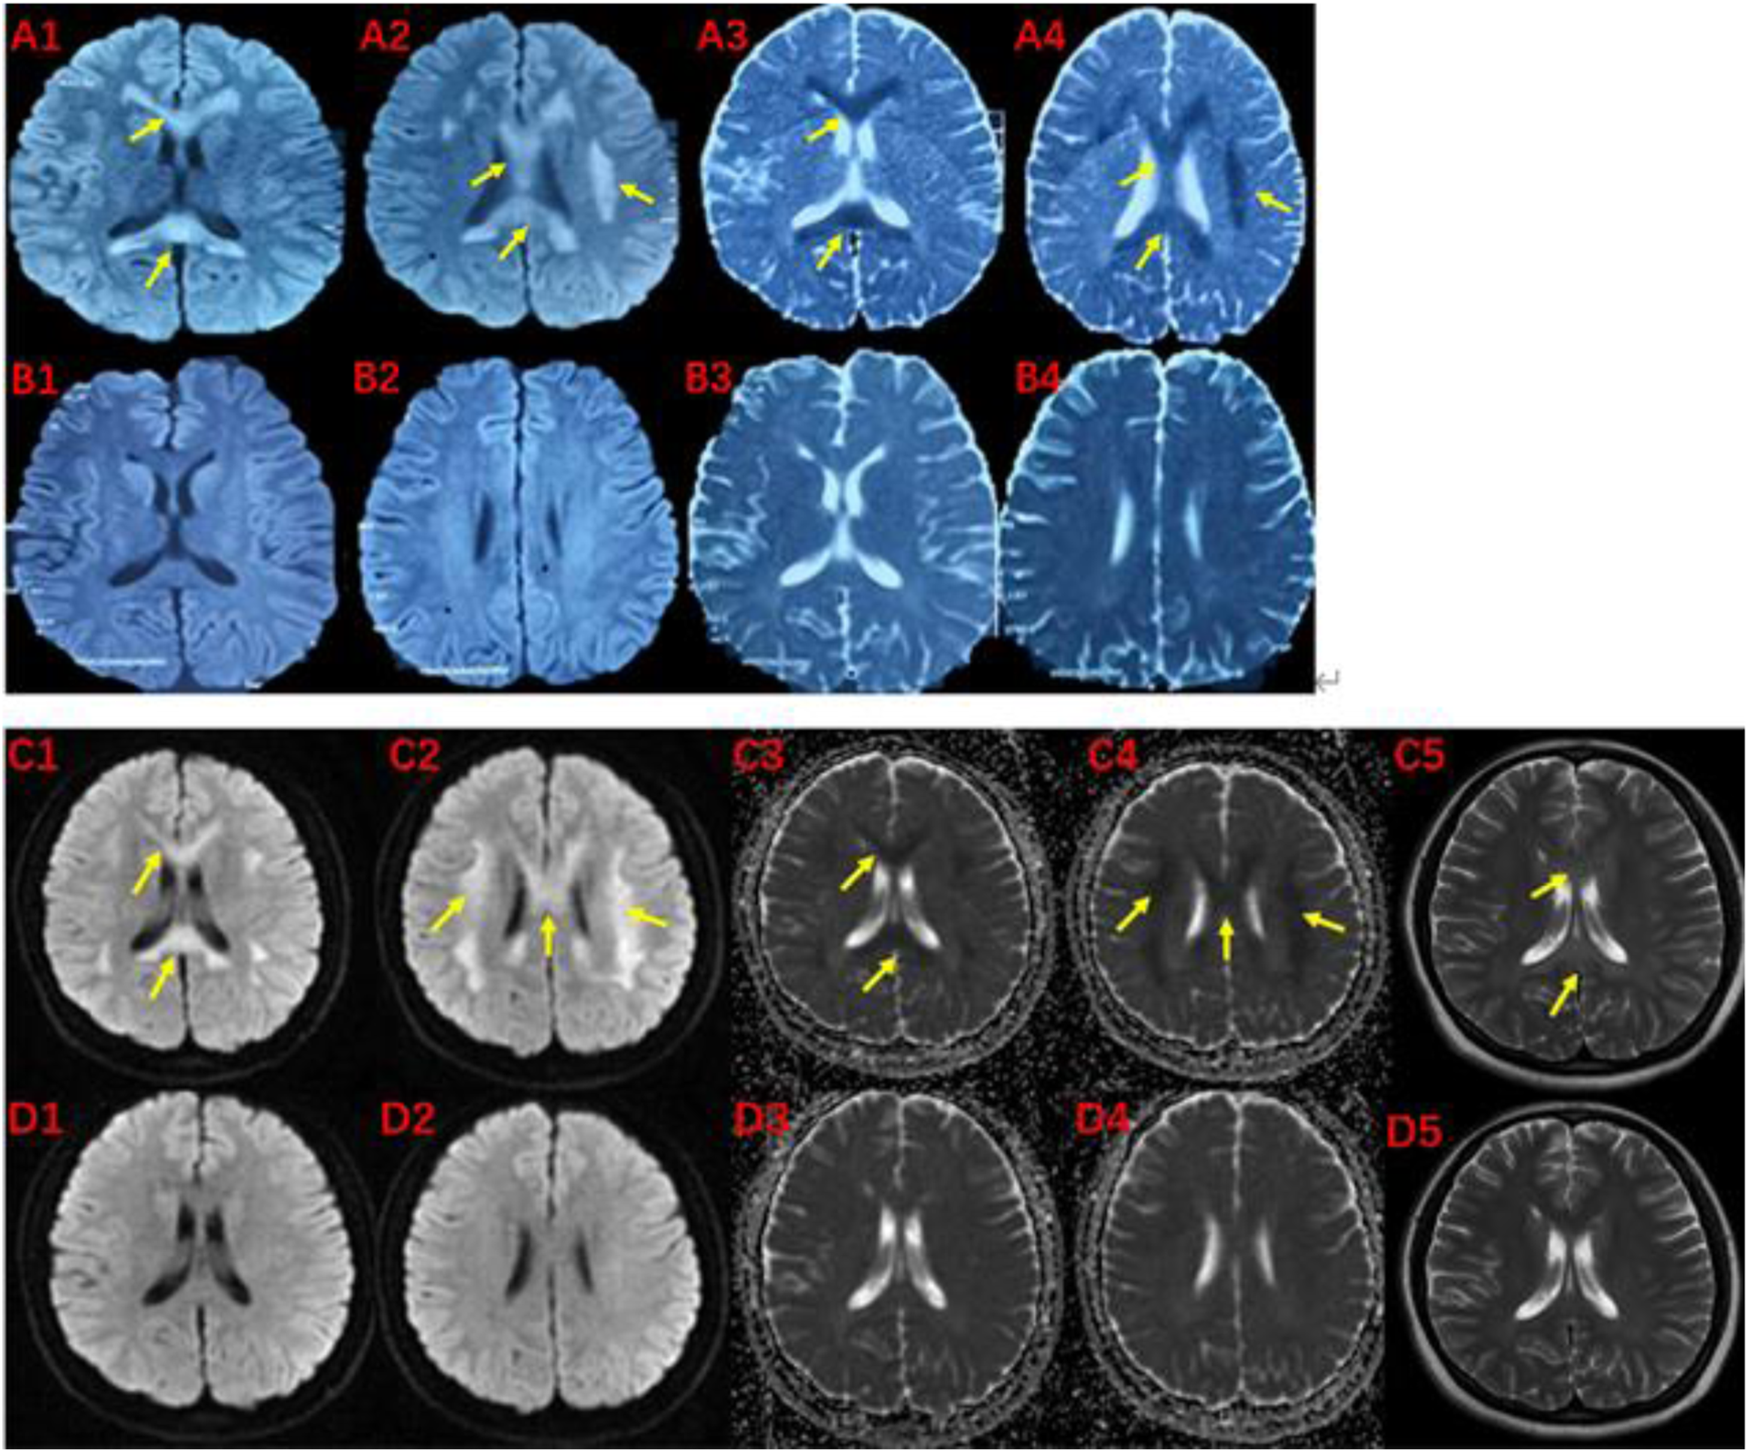

FIGURE 2. MRI of the proband (III-1) before and after the onset of the disease at 19 (A, B) and 27 (C, D) years of age.The brain MRI showed high intensities in bilateral white matter in the centrum semiovale and corpus callosum on diffusion-weighted (A1,A2,C1,C2), T2-weighted (C5), and low intensities on apparent diffusion coefficient images (A3,A4,C3,C4). These abnormal intensities disappear within two weeks (B1-B4 and D1-D5). The yellow arrow indicates involved structures.

The pedigree of the family is depicted in Figure 1. The proband (III-1) was a 27-year-old female with a history of two seizures after a fever in early childhood, but specific details were unknown. The grandfather and father of the proband also had a suspected history of seizures in childhood. The patient had a sudden onset of recurrent episodes of impaired speech fluency at the age of 19, which lasted for several hours and then resolved spontaneously. These episodes were exacerbated by no apparent trigger and were accompanied by gaze in both eyes (specific directions not available), right-sided mouth, closed teeth, stiff neck, and preserved consciousness during the episodes. Physical examination was negative for all pathological signs. Brain MRI showed abnormal intensities in bilateral white matter in the centrum semiovale and corpus callosum on diffusion-weighted, T2-weighted and apparent diffusion coefficient images, consistent with an acute demyelinating lesion (Figures 2A). Full-length sequencing of mitochondrial DNA was negative. The patient received steroids therapy with dexamethasone 10 mg and methylprednisolone 500 mg to alleviate symptoms, which did not recur. After 13 days, the cranial MRI showed complete normalization of the lesion (Figures 2B). After this infection with coronavirus at the age of 27, the patient developed fever up to 38.8°C, accompanied by generalized muscle aches and weakness. Three days after the infection, she experienced another episode of impaired speech fluency lasting more than 10 min, subsiding afterwards.

On blood, urine and stool tests, liver and renal function, thyroid function, blood biochemistry (including electrolytes such as potassium, sodium and chloride), full viral series, ANCA, antiphospholipid antibodies, homocysteine, C-reactive protein, erythrocyte sedimentation rate, glycated hemoglobin, and urine and stool routine were normal. Electrocardiography (ECG), echocardiogram, abdominal ultrasound, gynecological ultrasound and chest CT were also normal. The abnormal laboratory findings were as follows: white blood cell count:3.44*10^9/L, lymphocyte count: 0.83*10^9/L.The total T-cell count was 446.36/ul, T-helper cell count was 262.32/ul, T-suppressor/cytotoxic cell count was 136.35/ul and total B-cell count was 49.38/ul.The video electroencephalogram (EEG) showed a slight enhancement of slow waves in the theta band. Brain MRI showed abnormal intensities in bilateral white matter in the centrum semiovale and corpus callosum on diffusion-weighted, T2-weighted and apparent diffusion coefficient images, consistent with an acute demyelinating lesion (Figures 2C). We initially considered mild encephalopathy with reversible splenic lesions (MERS) due to the presence of neurological symptoms and extensive central nervous system demyelinating changes following the infection; However, considering that two immediate relatives had a history of seizures, we were unable to exclude the possibility of a genetic disorder. Therefore, along with general examination, we performed genetic testing. Whole exome sequencing of the proband revealed a missense mutation (MYRF- Q403R) at codon 403 of the MYRF gene: c.1208A>G (p.Gln403Arg) (Figure 3), resulting in an amino acid change from glutamine to arginine. The latest version of the Criteria and Guidelines for Interpretation of Genetic Variants (Richards et al., 2015) published by the American College of Medical Genetics and Genomics (ACMG) determined that the variant is likely pathogenic and is registered as NM_001127392: c.1208A>G(p.Gln403Arg). Meanwhile, the bioinformatics software REVEL predicted this variant as deleterious with a predicted value of 0.896.

Based on the patient’s history, clinical presentation, neurological examination, cranial MRI and genetic testing, the diagnosis of MMERV was made. Based on previous experience in the treatment of demyelinating diseases and the available evidence-based medical evidence, we treated with steroids regimen as follows: methylprednisolone 500 mg intravenously once a day for 3 days, there after the dose ladder was halved sequentially for 3 days each, and when it was reduced to less than 120 mg, it was switched to oral prednisone acetate 60 mg, still halving each dose for 3 days until discontinuation of the drug. Patient had no adverse reaction during treatment. The brain MRI lesion was completely normalized after 1 week (Figures 2D). Two carriers of the mutation were identified: Individual I-1 (grandfather of the proband) and Individual II-1 (father of the proband).

Laboratory tests for MMERV are generally not helpful in making a diagnosis. However, the disease exhibits distinct radiological features. Initially, Brain MRI showed abnormal intensities in bilateral white matter in the centrum semiovale and corpus callosum on diffusion-weighted, T2-weighted and apparent diffusion coefficient images, consistent with an acute demyelinating lesion (Figure 2). These extensive lesions have generally returned to normal within 1 week. Therefore, the presence of extensive myelin vacuolation on MRI should prompt consideration of the MYRF variant.